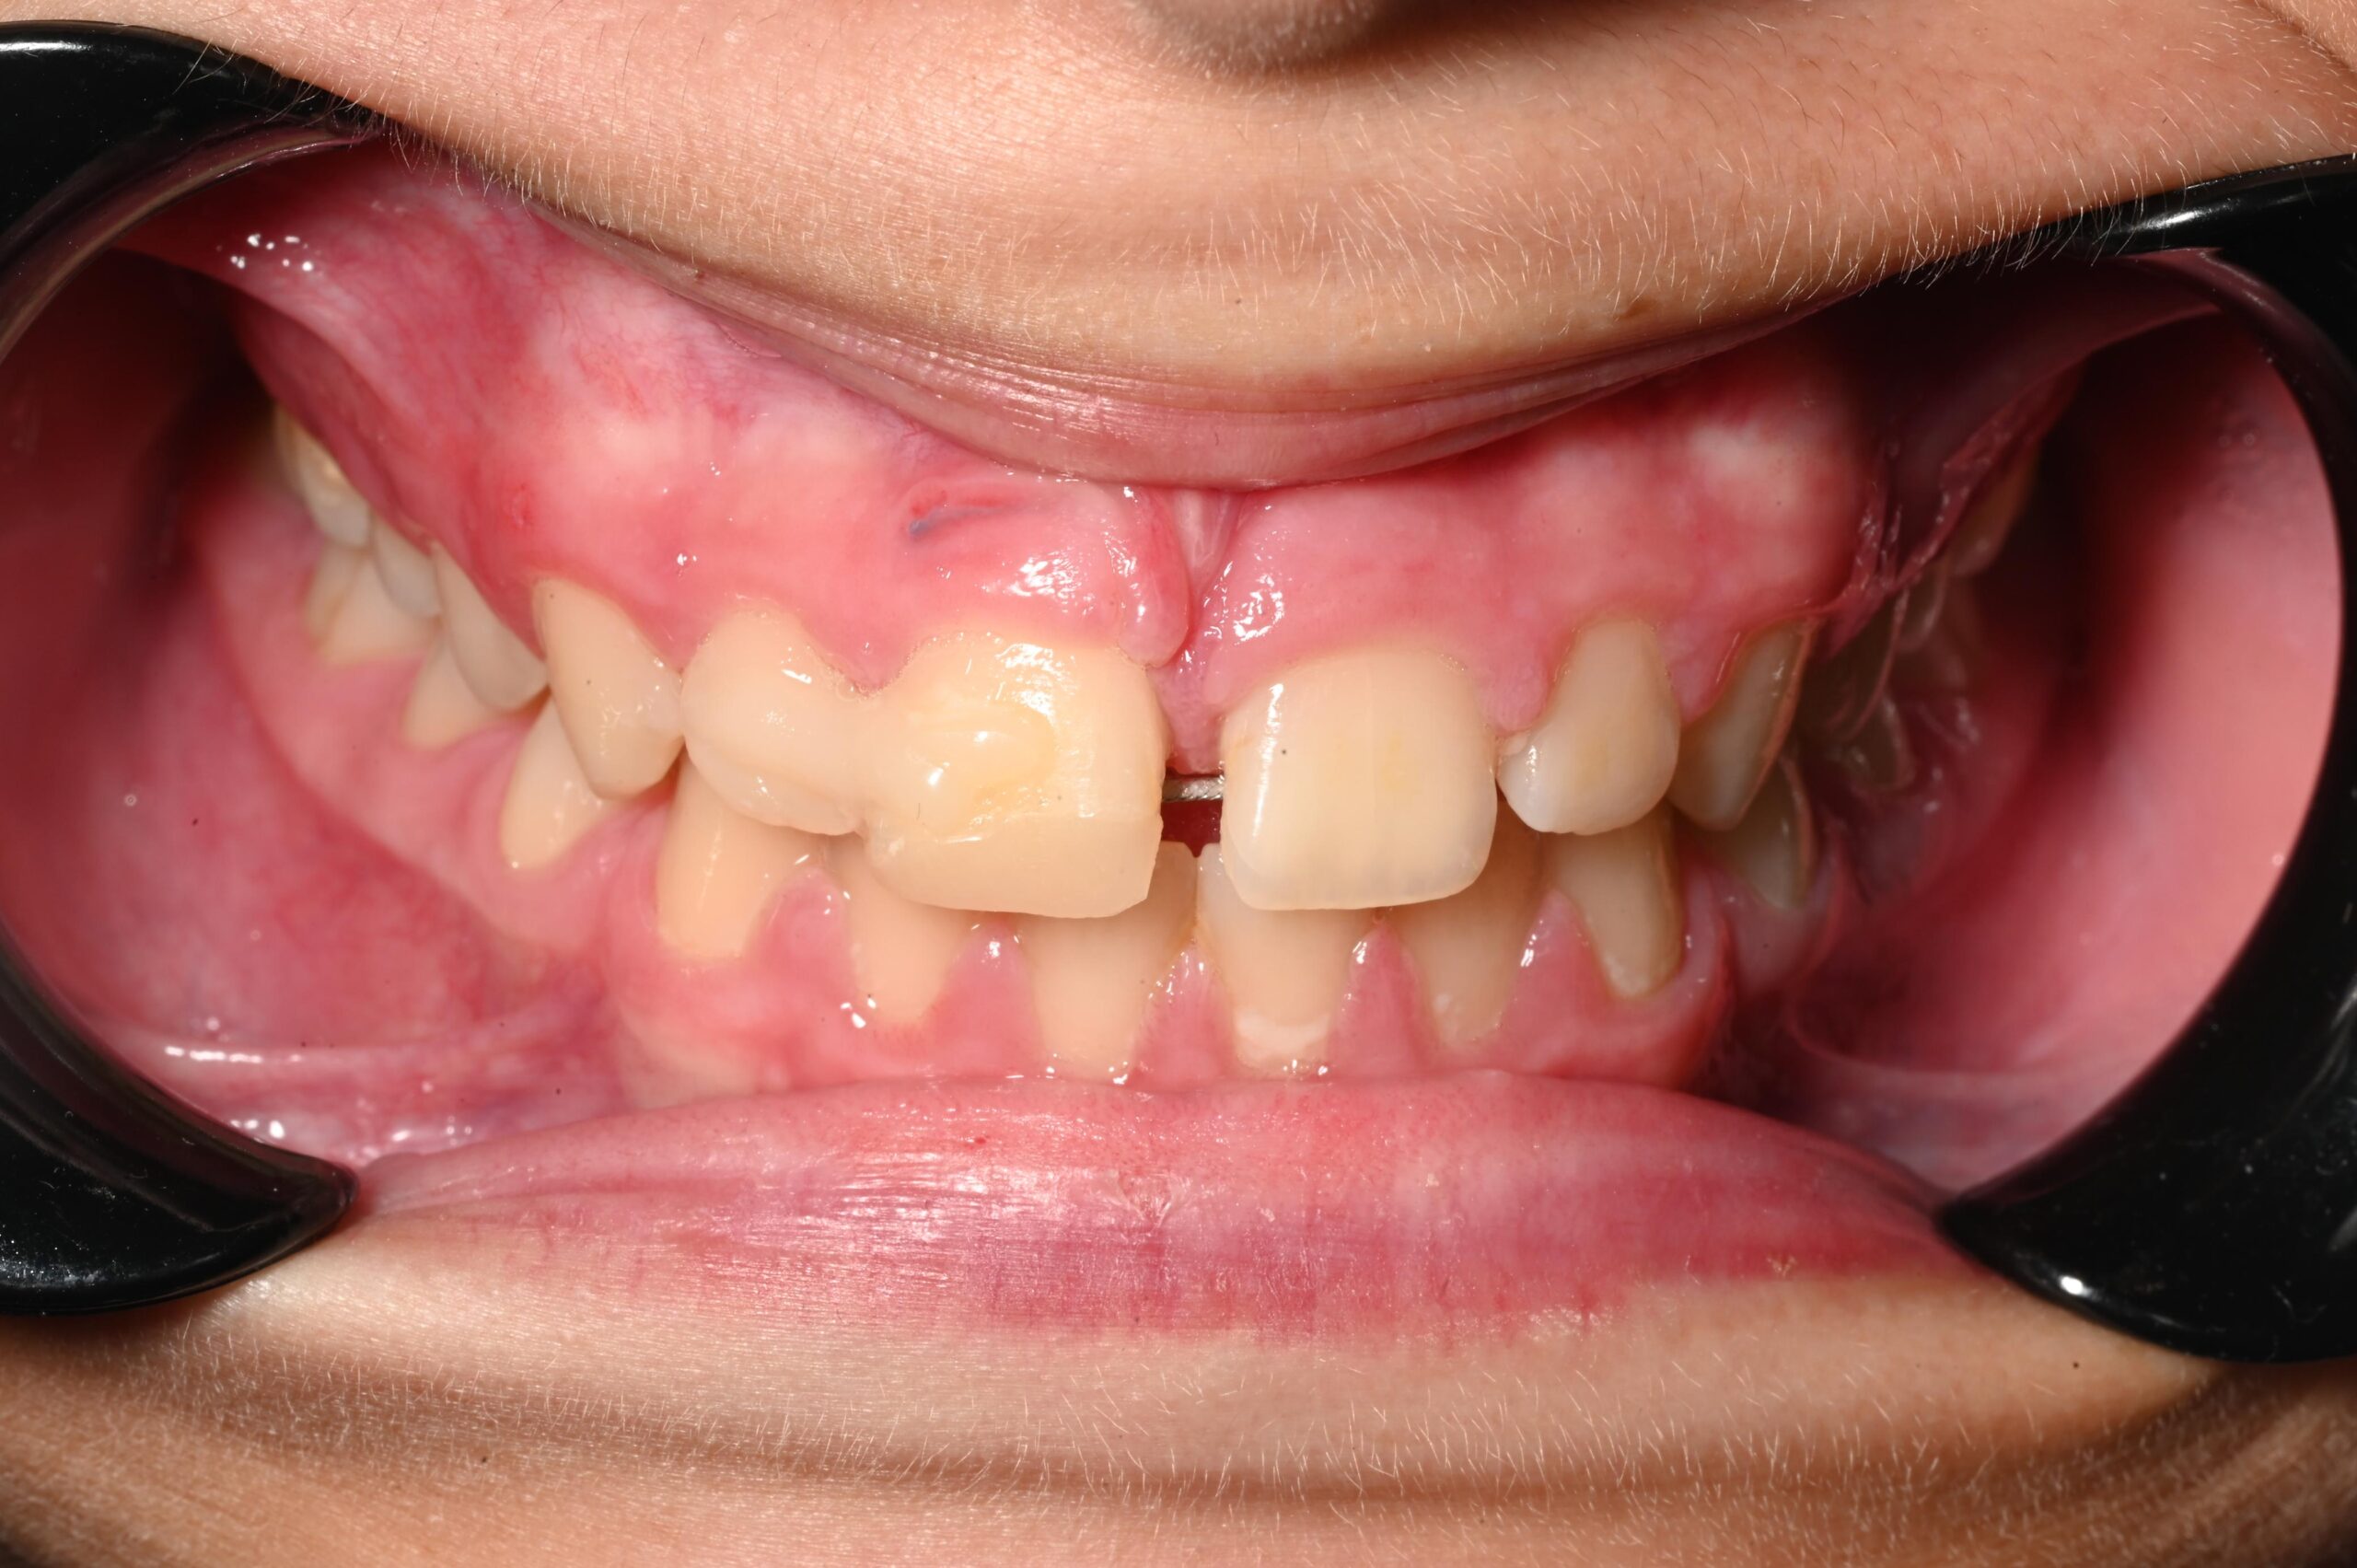

Dhëmbi, falë ruajtjes së duhur, u gjend në gjendje optimale për reimplantim. Reimplantimi u realizua brenda 15 minutash nga trauma, duke e vendosur këtë rast në kategorinë me probabilitet më të lartë suksesi afatgjatë, sipas protokolleve ndërkombëtare të traumave dentare.

2. Suturimi i indeve të buta

Për të krijuar një mbyllje të sigurt të plagës dhe për të stabilizuar strukturat e dëmtuara, u krye suturimi i indeve të buta. Ky hap ishte thelbësor për të parandaluar infeksionin, për të ruajtur stabilitetin e zonës dhe për të lehtësuar procesin e shërimit.

3. Splintimi stabilizues – kombinim i kompozitit dhe telit ortodontik

U përdor një teknikë e kombinuar splintimi:

• Kompozit në anën vestibulare, i cili jep fleksibilitet dhe estetikë.

• Tel ortodontik në anën palatinale, i cili përforcon stabilitetin pa e ngurtësuar dhëmbin në mënyrë të tepruar.

Ky lloj splintimi i “butë” (flexible splint) është i rekomanduar në trauma të këtij lloji, sepse ndihmon në rigjenerimin e ligamentit periodontal.